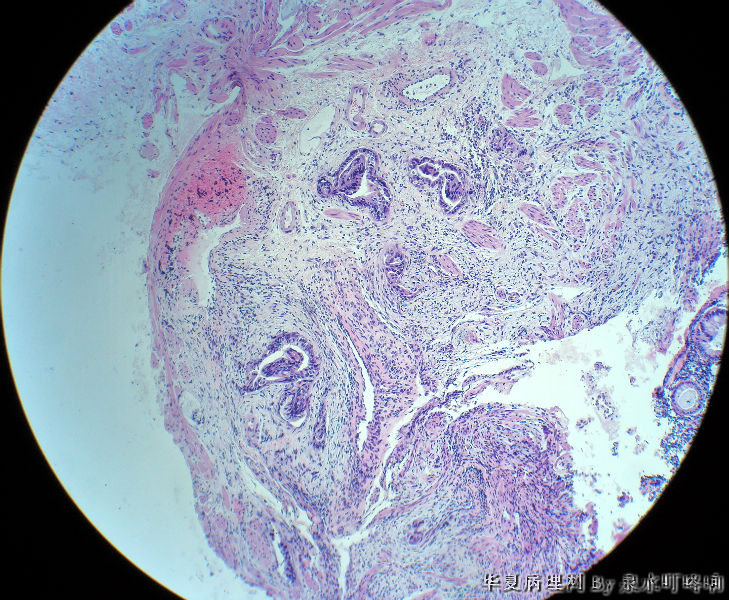

直肠活检

• 直肠活检图1

图1

女,49岁,大便变细2年,结肠镜示距肛门5厘米可见溃疡形成,弥漫肠管全周。

腺癌

纤维组织中可见异型腺体浸润,诊断腺癌。

可见异型腺体,疑为直肠腺癌

分化较好的腺癌。